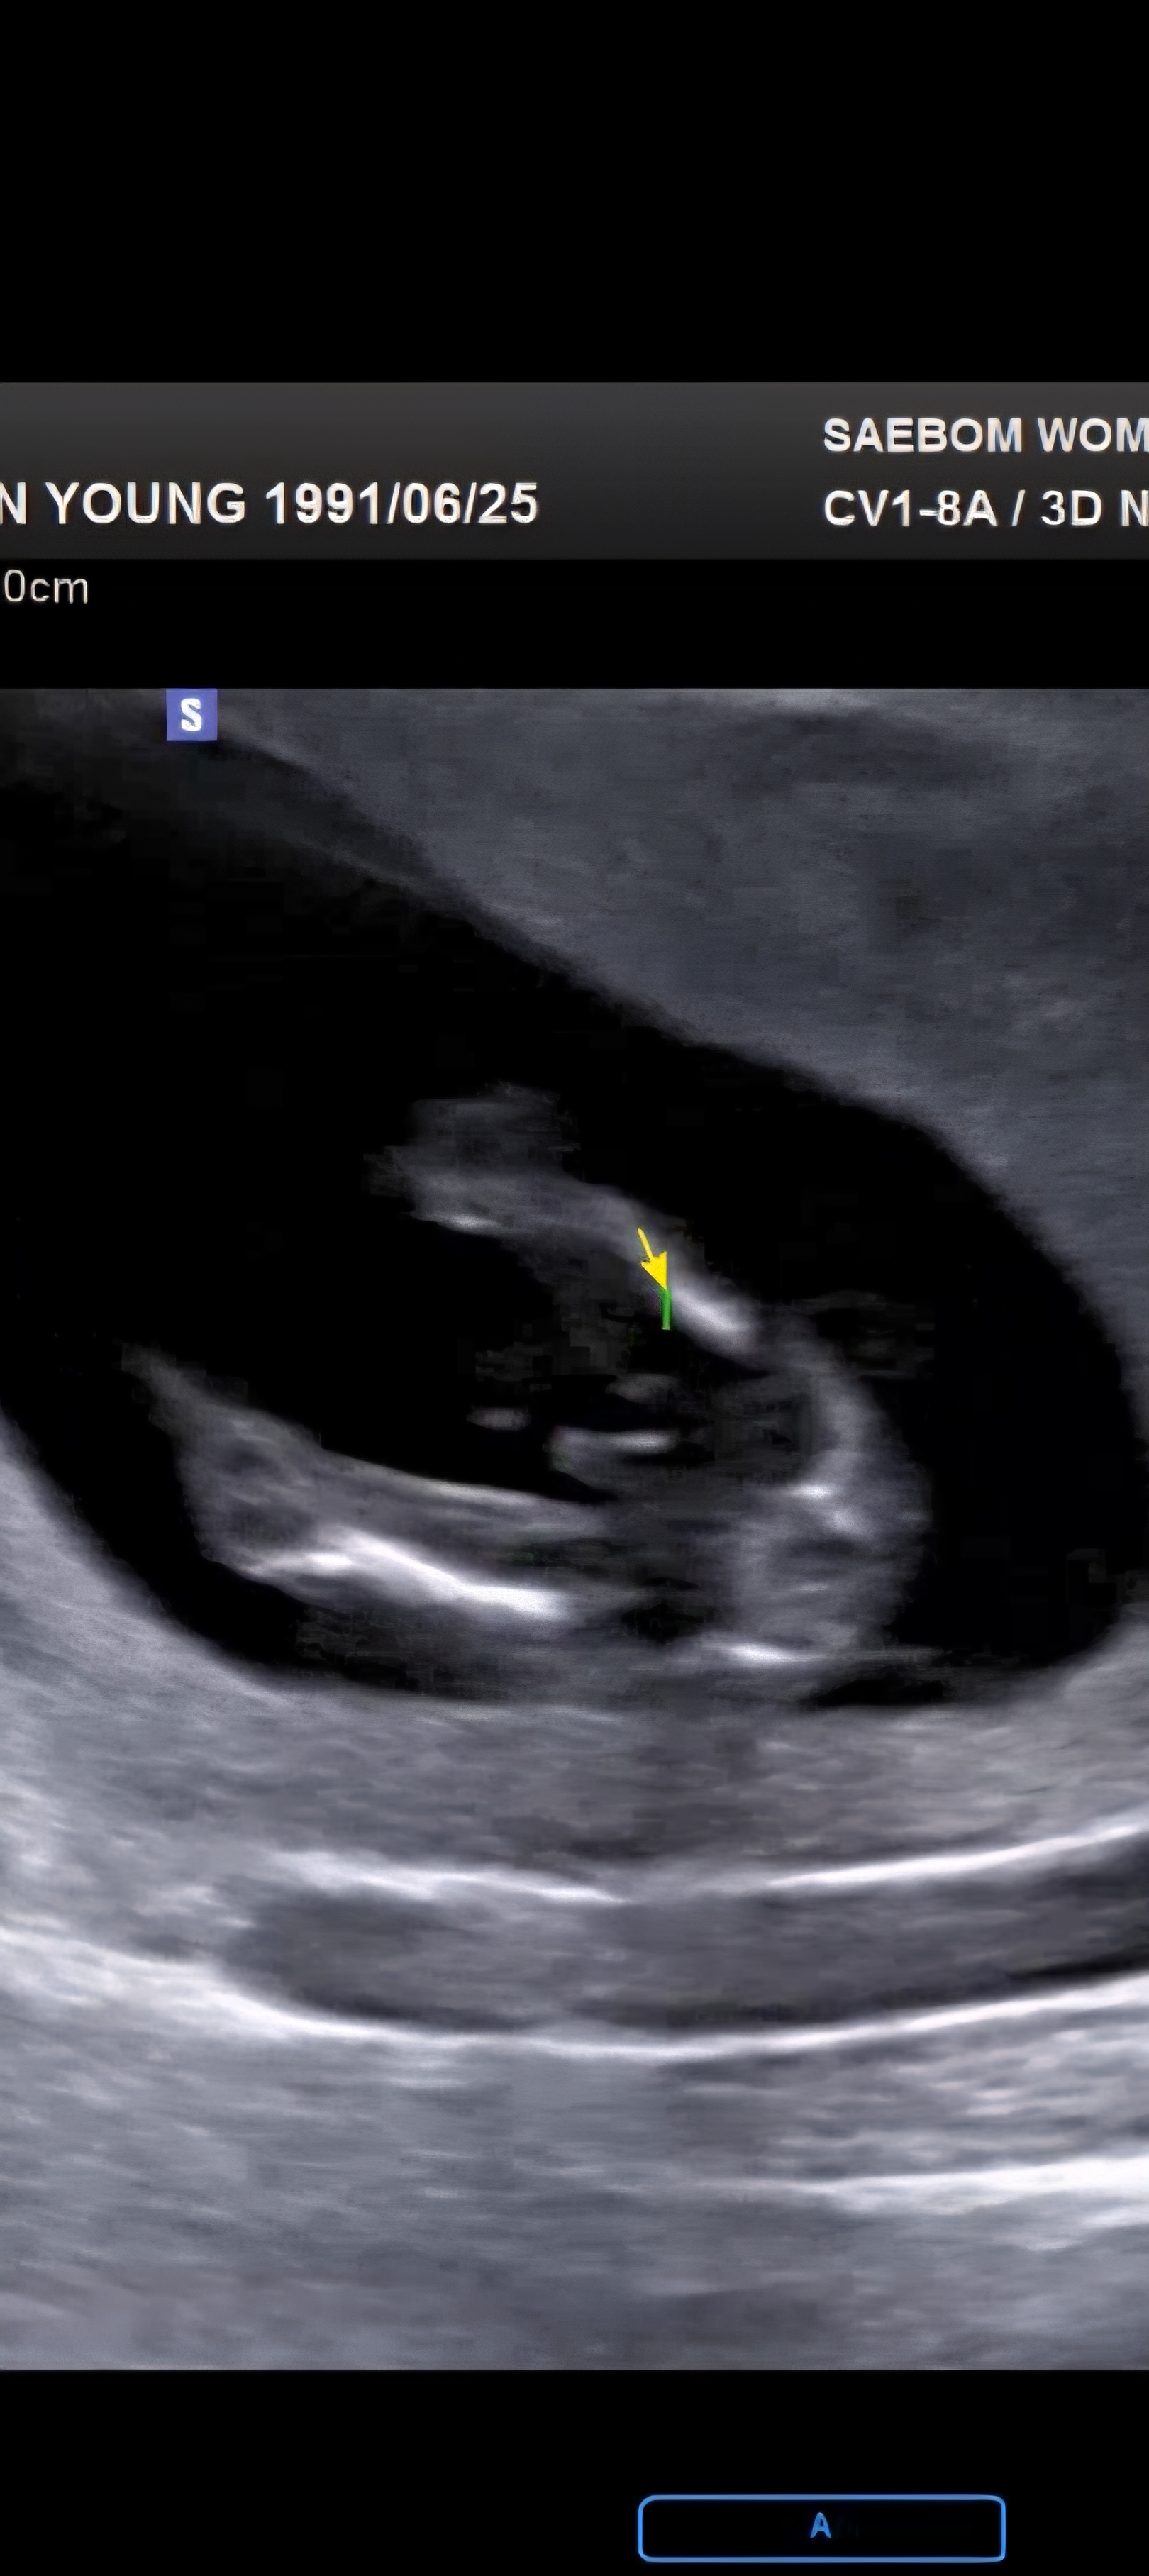

13주5일 초음파 사진인데요. 존재감이😅😅😅 없어질수도 있다고 들었는데..이정도는 반전없이 빼박 일까요? 많은 의견 부탁드려요!